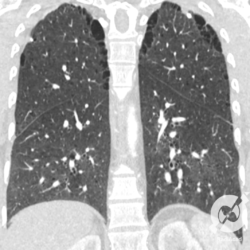

Esta é uma tomografia que mostra o que acontece num enfisema, que é a destruição dos espaços aéreos distais ao bronquíolo terminal. O mais comum é esta destruição ocorrer no centro do lóbulo, o chamado enfisema centrolobular, que na tomografia aparece como estas pequenas imagens hipoatenuantes, sem paredes definids, com distribuição esparsa nos pulmões, parecendo um roído de traça (a). Na periferia, a gente percebe um segundo tipo de enfisema, no qual a destruição do espaço aéreo ocorre mais na periferia do lóbulo, conhecido como enfisema parasseptal, que tem distribuição mais periférica (foto b, no pulmão direito), com aspecto que lembra um cerca de madeira). Eventualmente estas imagens podem confluir e formar lesões maiores, com aspecto de bolhas (b).

Aqui a gente tem no corte axial enfisemas centrolobular e parasseptal confluentes no ápice. Na reconstrução coronal, fica mais fácil entender o enfisema parasseptal, com aquela distribuição parecida com uma cerca de madeira, apresentando uma distribuição periférica nos lobos superiores.